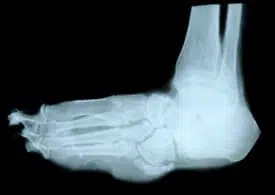

Diagnóstico

O diagnóstico do pé de Charcot pode ser feito com base na perda de forma e estrutura normal do pé e tornozelo. Isso pode ser visto no exame físico, e demonstrado através de raios-X ou ressonância magnética.